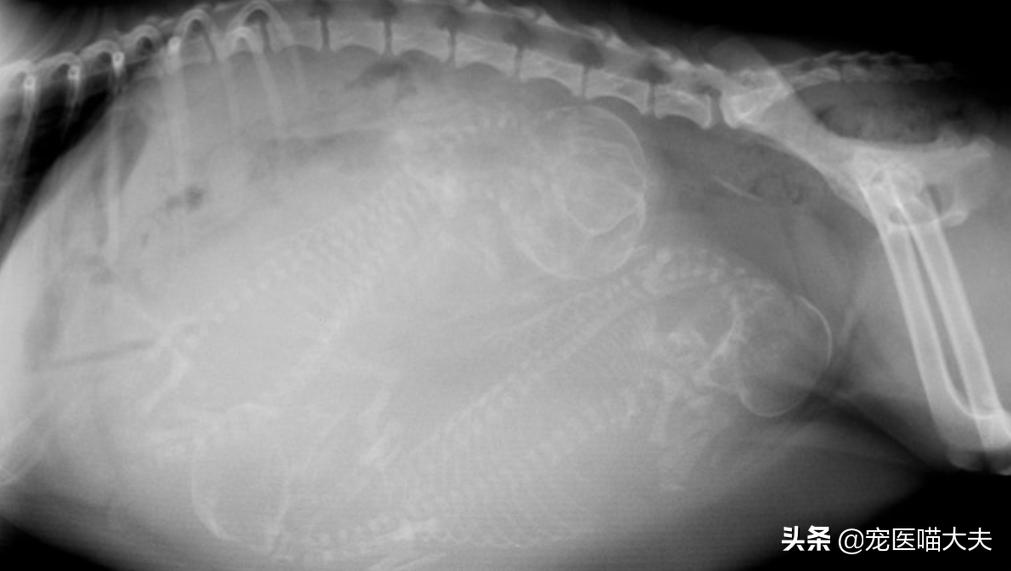

3、X射线检查

X射线检查一般用在雌性狗狗的怀孕后期,通过X射线检查,可以大约判断出狗妈妈子宫内小狗的数量;一般在55天之后进行X射线检查才可以准确判断出小狗的数量,因为在其之前,胎儿的颅骨和脊柱正在发育,且在X片上不可见,所以,对狗狗进行X射线检查时,掌握时间是非常重要的哦;另外,通过X射线检查也可判断狗狗是否有胎儿性难产或母体性难产的风险,比如胎儿是否过大和狗妈妈盆骨是否过窄等。

X射线检查怀孕的狗狗